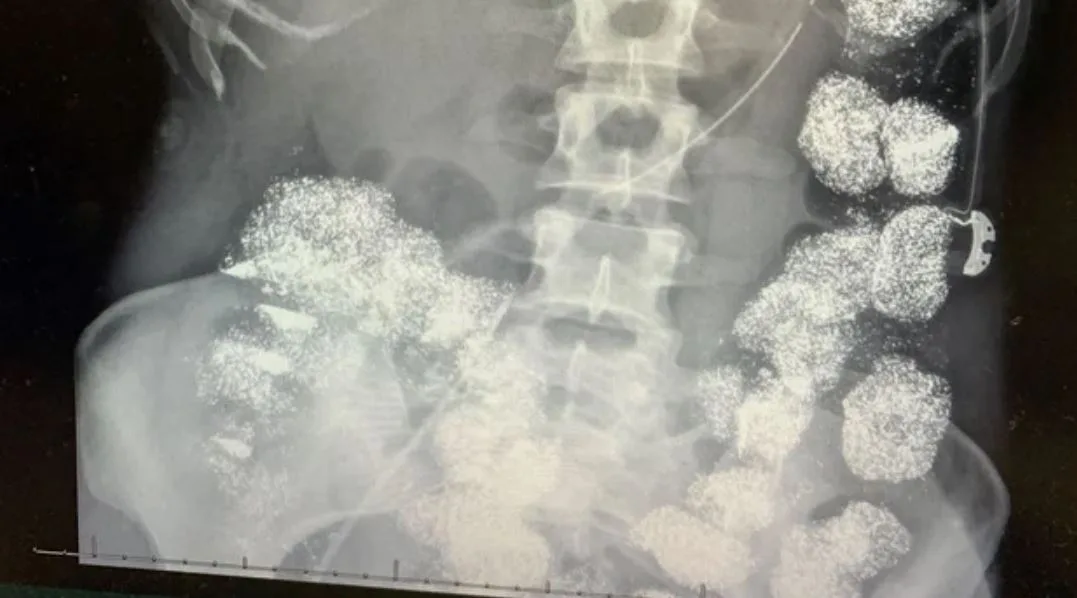

Eight days later doctors had a shocking diagnosis. Hannah’s colon was almost completely filled with lead – a toxic metal causing organ damage and death.

She was so full of lead there was no room in her stomach for food. It was even in her bones.

Hannah’s X-rays and scans were shown in court – her body a crime scene.

Doctors testified that Hannah had eight times the normal amount of lead in her system.